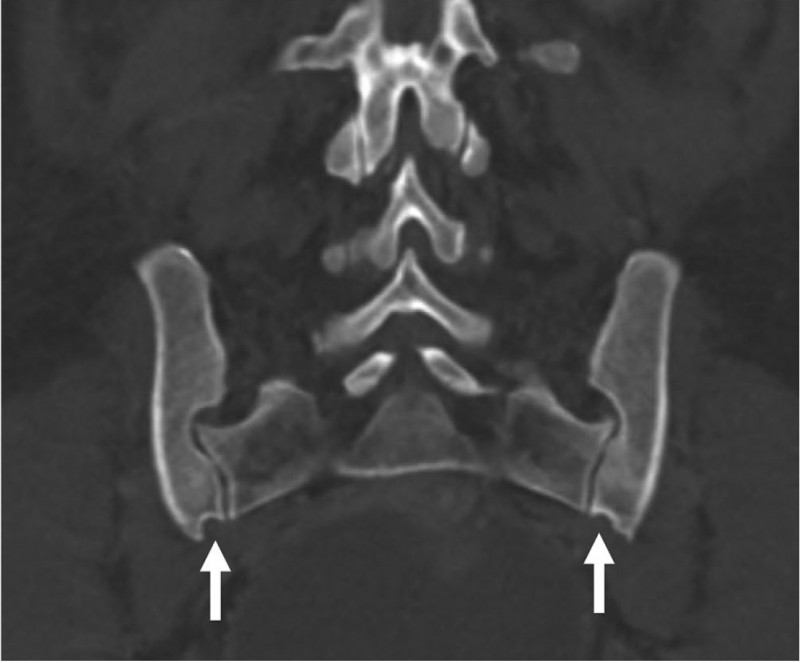

Fig. 3 from the publication: Coronal CT scan of a female pelvis showing the preauricular sulcus (white arrows).

A recent paper in the American Journal of Biological Anthropology,  co-authored by KLI group leader Barbara Fischer, challenges the long-held belief that certain pelvic bone features—often called "scars of childbirth"—can reveal a woman's history of pregnancy and birth. Researchers used CT scans to examine the pelvises of women with and without children, as well as men, and found that these bony traits were just as common in women who had never given birth as in those who had. The preauricular sulcus, a groove on the pelvic bone, was found in about half of all women but not in men, suggesting it is linked to sex rather than childbirth. Other features showed no clear connection to pregnancy or delivery. While urinary incontinence was more frequent among women who had given birth, it did not strongly correlate with pelvic bone changes. The study concludes that pelvic skeletal features are unreliable as markers of reproductive history, urging caution in their use for anthropological research.